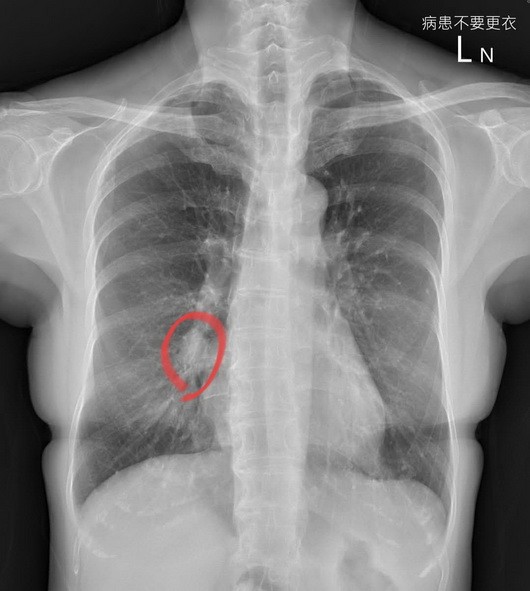

▼红圈处是3公分肺癌。

医生指出,X光一照看完觉得有问题,“让大家找看看在哪里”;安排后续的计算机断层CT检查,发现是3公分的肺癌,大概第二期或三期。